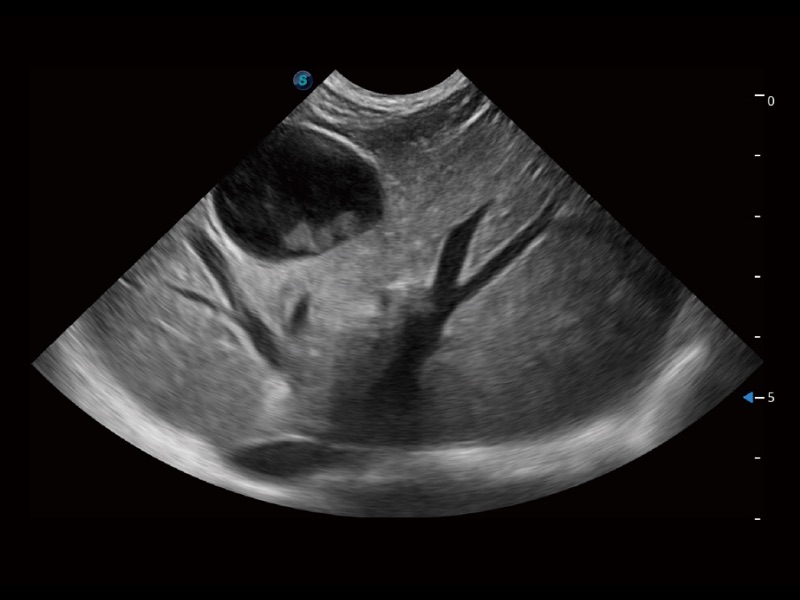

(犬)四腔心